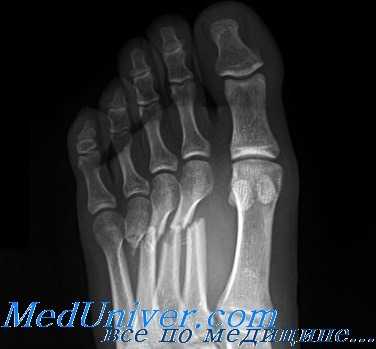

Для выявления этих переломов обычно достаточно снимков в прямой, боковой и косой проекциях. Часто они сопровождаются тыльной угловой деформацией вследствие тяги внутренних мышц. Наличие везалиевой кости (вторичный центр окостенения) у основания V плюсневой кости можно спутать с переломом. Вторичные центры окостенения, как правило, гладкие, закругленные и наблюдаются с двух сторон; часто они имеют склерозированные края. Сначала стрессовые переломы рентгенологически могут не определяться. Однако через 2—3 нед линия перелома обычно становится заметной, а через 4 нед выявляется костная мозоль.

(Слева) При прицельной рентгенографии стопы в передне-задней проекции определяются необычный продольный перелом головки 4-й плюсневой кости и ее вывих. Пациентка упала с велосипеда, на котором ехала босиком.

2. Рентгенография при переломе плюсневых костей:

• Рекомендуется рентгенографию выполнять в трех проекциях: передне-задней, косой и боковой

• Перелом может выявляться лишь в одной проекции